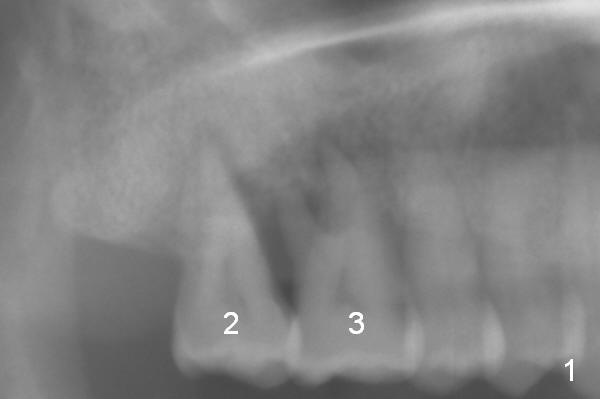

A 52-year-old lady is pleased with the implant at #15 and requests implants at #2 and 3 next (Fig.1,2). Due to severe bone resorption, bone level should be uneven circumferentially. The implants will be placed as apical as possible, i.e., buried in the native bone. If implant threads are exposed in small region, they will be covered by allograft (Fig.3 pink circles). The size of the abutments is shown in red. Clindamycin will be used for socket disinfection.